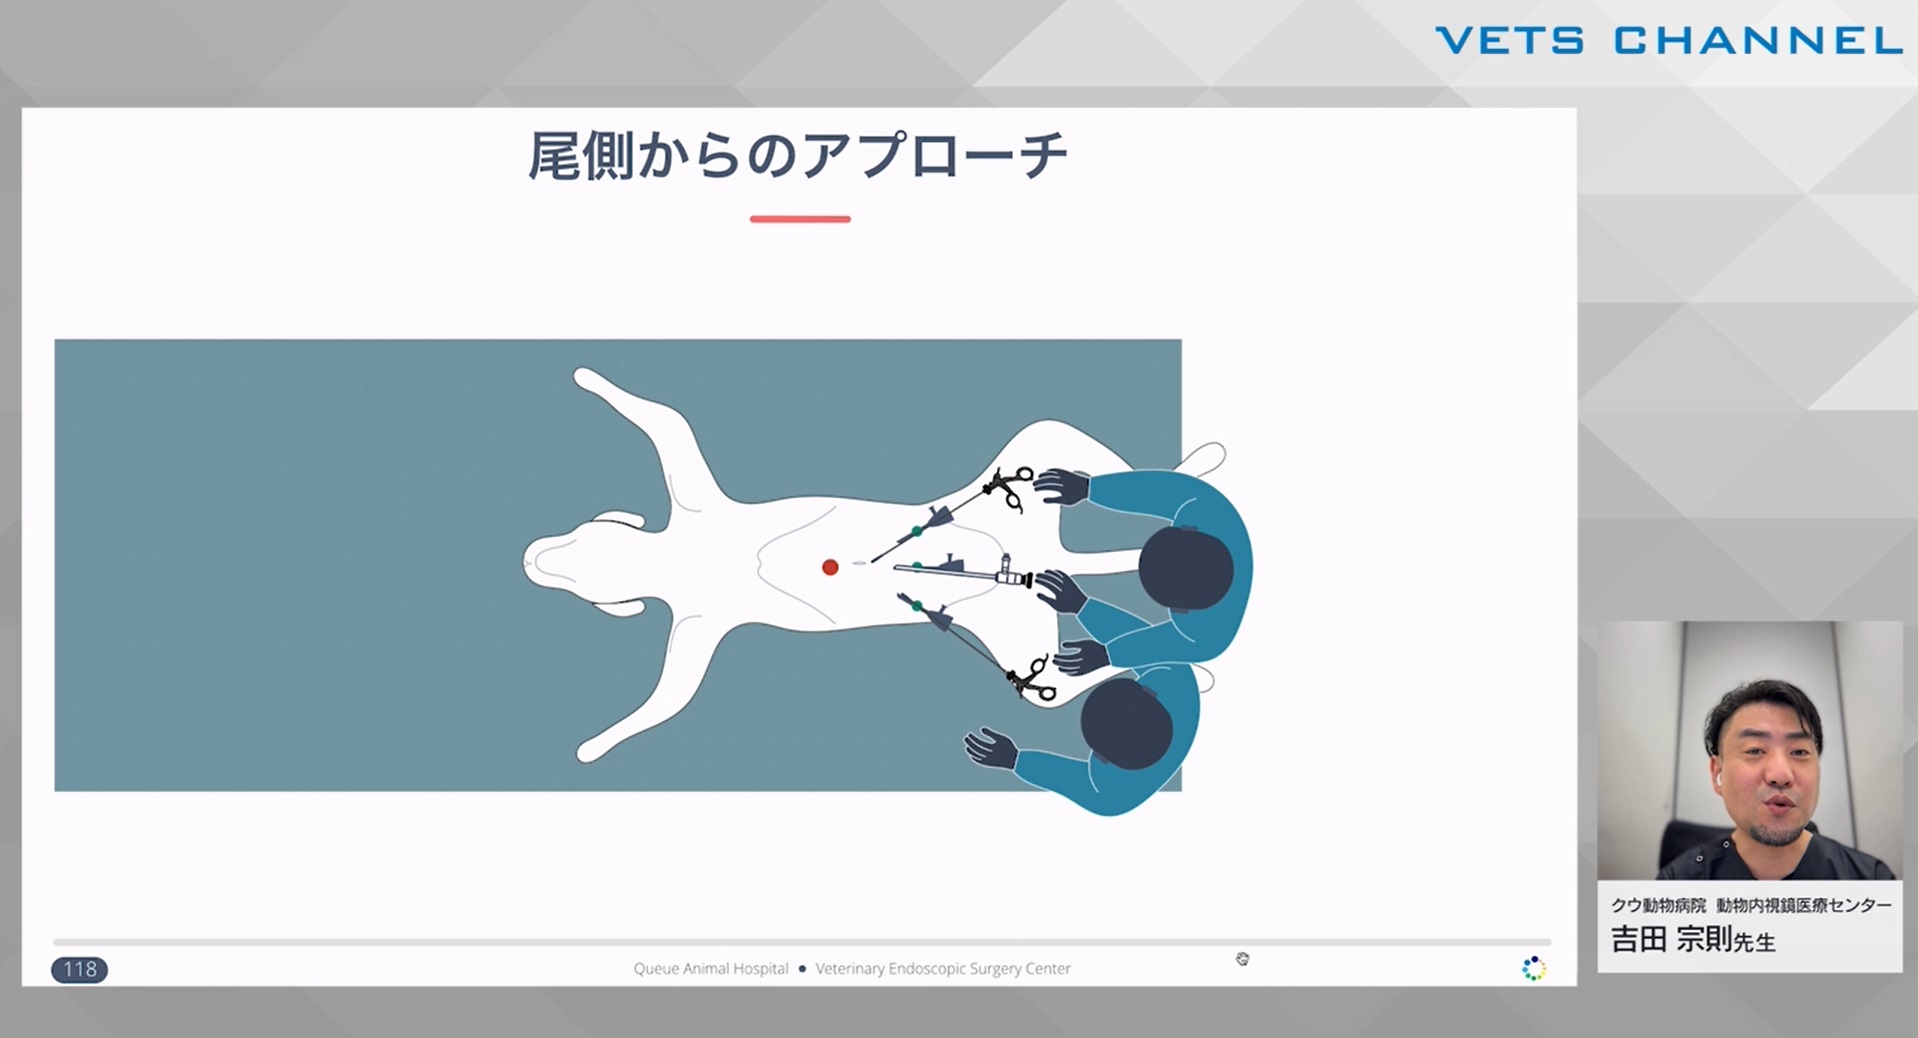

初学者のための腹腔鏡テクニック 第4回:「円滑な手術を実施するために」

- テクニック

- 内視鏡科

吉田 宗則先生(クウ動物病院 動物内視鏡医療センター)

46分

2025/01/03

初学者のための腹腔鏡テクニック 第3回:「トロッカーと気腹」

- テクニック

- 内視鏡科

吉田 宗則先生(クウ動物病院 動物内視鏡医療センター)

60分

2025/01/03